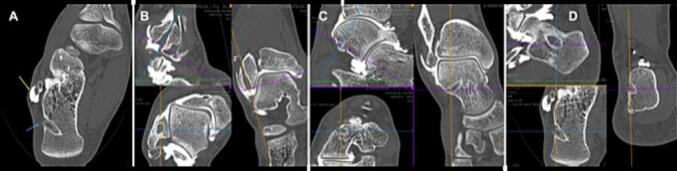

Because of the ligament lesions and the persistent instability despite rehabilitation, in May 2018 the patient underwent arthroscopic reconstruction of the lateral ligaments of the ankle with a gracilis autograft using the technique by Guillo et al. modified by Lopes et al. [12], [13], [14]. The procedure was performed with the patient in the supine position, with a pneumatic tourniquet (on the thigh), by a surgeon experienced arthroscopic ankle surgery. Classic arthroscopic material was used (4-mm 30° arthroscope; 3 mm bone/soft tissue shaver). The graft was attached to the talus and calcaneum with tenodesis screws (Bio-Tenodesis Screw®, Arthrex, Naples, Fl, USA). Peroneal fixation was achieved with a cortical endobutton (ACL TightRope®, Arthrex, Naples, Fl, USA). The rest of the arthroscopic exploration of the ankle was normal. Immediate postoperative weight-bearing was allowed with a walking boot for 2 weeks. There were no prophylactic antithrombic. Rehabilitation was begun on postoperative week 2. Seven months after surgery, the ankle was stable, flexible, and pain free, and the patient had returned to all activities (including basketball) with no limitations or discomfort. The patient had another high-energy basketball injury to the right ankle in November 2019. There was no other medical history, his BMI was still normal (=21.5 kg/m2). The clinical examination showed frontal and sagittal plane instability without pain or stiffness. Despite rehabilitation, the ankle was unstable and the patient was apprehensive during sports. The MRI showed a CFL tear and a heterogenous appearance to the ATFL with no clear tear. Ultrasound and arthrography showed a complete ligament graft tear. There were no osteochondral lesions or other ligament injuries (syndesmosis, deltoid). An analysis of the bone tunnels did not show any malposition or widening [12], [13], [14] (Fig. 1).

Fig. 1.

A,B,C,D Imagerie Pre-op.